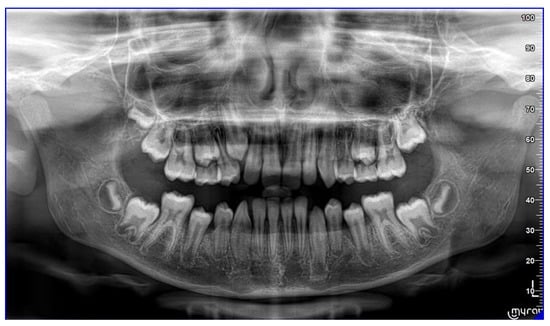

The patient is an 11-year-old female, in late mixed dentition. Clinical examination revealed acceptable oral hygiene, absence of functional anomalies and oral habits, the presence of deciduous molars (5.5 and 6.5), and erupting permanent teeth. The intraoral examination showed a molar and canine Angle class II on both sides, increased overjet, posterior unilateral functional crossbite on the right side, lower/upper midline deviated to the right/left of 2 mm, and increased overbite (5 mm) (Figure 6). The most important problem was that 1.3 was not in the arch, while the contralateral 2.3 had been present for more than 6 months. Diagnostic X-ray confirmed the 1.3 eruption delay. (Figure 7).

Figure 6. Clinical case treated with Invisalign© aligners. Intraoral views from ClinCheck. Frontal, upper, and lower occlusal and lateral view of occlusion before the beginning of treatment.

Sensors 21 01856 g006